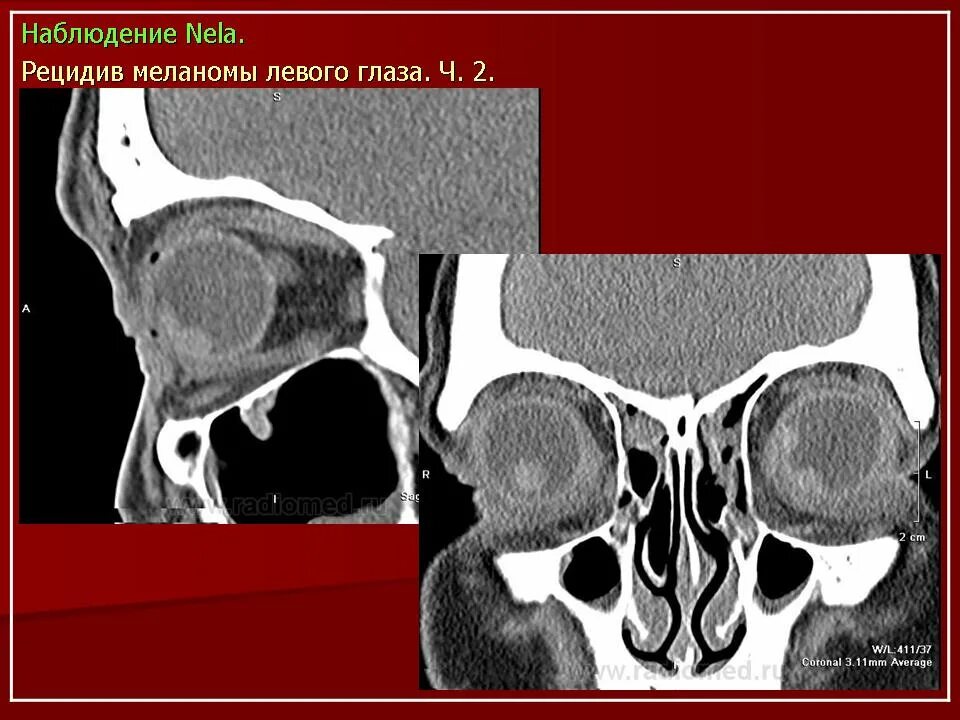

Данные кт